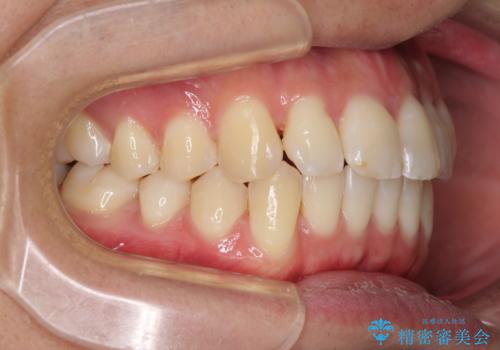

- 前歯のデコボコと若干口元が突出していることを気にして来院された患者様です。

全体的に軽微な叢生が認められ、口元もやや前方に突出していたため、インビザラインでのIPR(歯と歯の間を削る)と歯列全体の後方移動によって歯並びを整えることとしました。

上下ともに歯列の幅が狭かったため、側方に拡大することで前歯のデコボコや突出感を解消するためのスペースを獲得することができました。

歯並びが改善したことはもちろん、咬み合わせの改善まで実感することができ、患者様には大変満足していただけました。